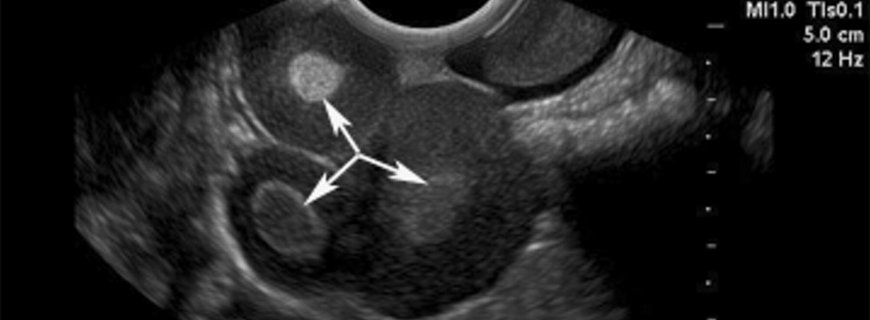

Kolposkopi nedir?

Kolposkopi, özel bir mikroskop ile sağlanan büyütme altında ve asetik asit uygulaması ile rahim ağzının hücresel değişiklikler açısından görsel muayenesidir. Kolposkopide görünen anormal alanlardan biyopsiler alınarak patolojik tanı belirlenir.